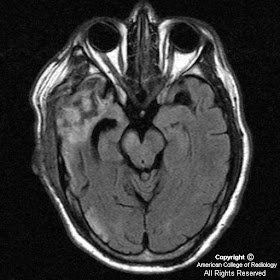

Figure 2, Figure 3, Figure 4, and Figure 5 : T2-weighted FLAIR images obtained 60 days after the initial infarct demonstrate decrease in cytotoxic edema, evolution of intraparenchymal hemorrhage, and ex vacuo dilatation of the right lateral ventricle. Following the right corticospinal tract caudally, there is increased T2 signal to the level of the pons representing gliosis as well as atrophy of the cerebral peduncle, compatible with Wallerian degeneration.

Diagnosis: Wallerian degeneration

Wallerian degeneration is antegrade destruction of axons and myelin sheaths following damage to the proximal portion of the axon or the cell body. The most common cause of Wallerian degeneration in the brain is infarction. Other causes include hemorrhage, trauma, neoplasm, and white matter disease. Dead tissue is phagocytized with resultant gliosis throughout the affected white matter tract, which can be visualized as hyperintensity on FLAIR sequences. There is no enhancement after contrast administration. Wallerian degeneration can be demonstrated 2-6 months after the initial insult, often as an atrophied cerebral peduncle with increased T2 signal along the involved corticospinal tract.

Wallerian degeneration of the corticospinal tract (or pyramidal tract) indicates severe damage and thus marked motor function impairment. It has been shown that progressive Wallerian degeneration as demonstrated on MRI is associated with persistent moderate to severe hemiparesis.